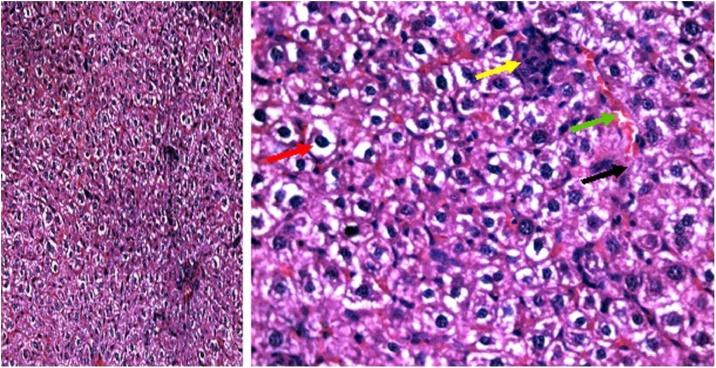

The current research aims to demonstrate the therapeutic effect of sour orange albedo extract (SOAE) and two flavanones loaded-tetraethylorthosilicate (TEOS) using sol-gel technique, in adose100 mg/kg body weight taken orally or45 days against acrylamide (ACR)toxicity in rats. This was achieved through measuring the activities of specific biochemical parameters related to liver functions in tissue of ACR intoxicated rats as compared to normal one. Liver functions included alanine and aspartate aminotransferases, antioxidants and oxidative stress biomarkers; superoxide dismutase, catalase, glutathione and lipid peroxide (malondialdehyde, MDA). Moreover, histological examination of liver was performed to confirm the biochemical findings. The present results clearly indicated disturbances in all biochemical parameters, such as increase in the liver function enzyme activities and MDA level. Results of ATPase enzyme activities revealed significant decrease in ACR intoxicated rats and liver biomarker enzymes declared significant decrease. On the other hand, treatment of intoxicated rats with the previous different nano-particles natural product demonstrated improvement in all biochemical parameters under investigation.

当前的研究旨在证明酸橙皮提取物(SOAE)和两种负载黄酮的原硅酸四乙酯(TEOS)(采用溶胶-凝胶技术制备)在以100毫克/千克体重口服给药45天的情况下,对大鼠丙烯酰胺(ACR)毒性的治疗效果。这是通过测量与正常大鼠相比,ACR中毒大鼠组织中与肝功能相关的特定生化参数的活性来实现的。肝功能包括丙氨酸和天冬氨酸转氨酶、抗氧化剂和氧化应激生物标志物;超氧化物歧化酶、过氧化氢酶、谷胱甘肽和脂质过氧化物(丙二醛,MDA)。此外,还进行了肝脏组织学检查以证实生化结果。目前的结果清楚地表明所有生化参数都出现了紊乱,如肝功能酶活性和MDA水平升高。ATP酶活性结果显示ACR中毒大鼠显著降低,肝脏生物标志物酶也显著降低。另一方面,用先前不同的纳米颗粒天然产物治疗中毒大鼠,结果显示所研究的所有生化参数都有所改善。